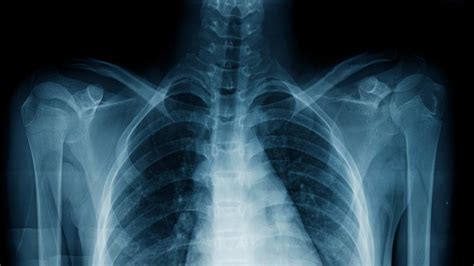

5. Bony Thorax and Soft Tissues

Finally, a normal chest X-ray should also show a normal bony thorax and soft tissues. The bony structures, including the ribs, vertebrae, and sternum, should appear intact without any fractures or lesions. The soft tissues of the chest wall, including the breasts and the muscles, should not show any signs of disease such as masses or thickening. The mediastinum, which contains the heart, trachea, esophagus, and other vital structures, should be of normal width and density, as an enlarged mediastinum can indicate serious conditions like lymphoma or aortic aneurysm.